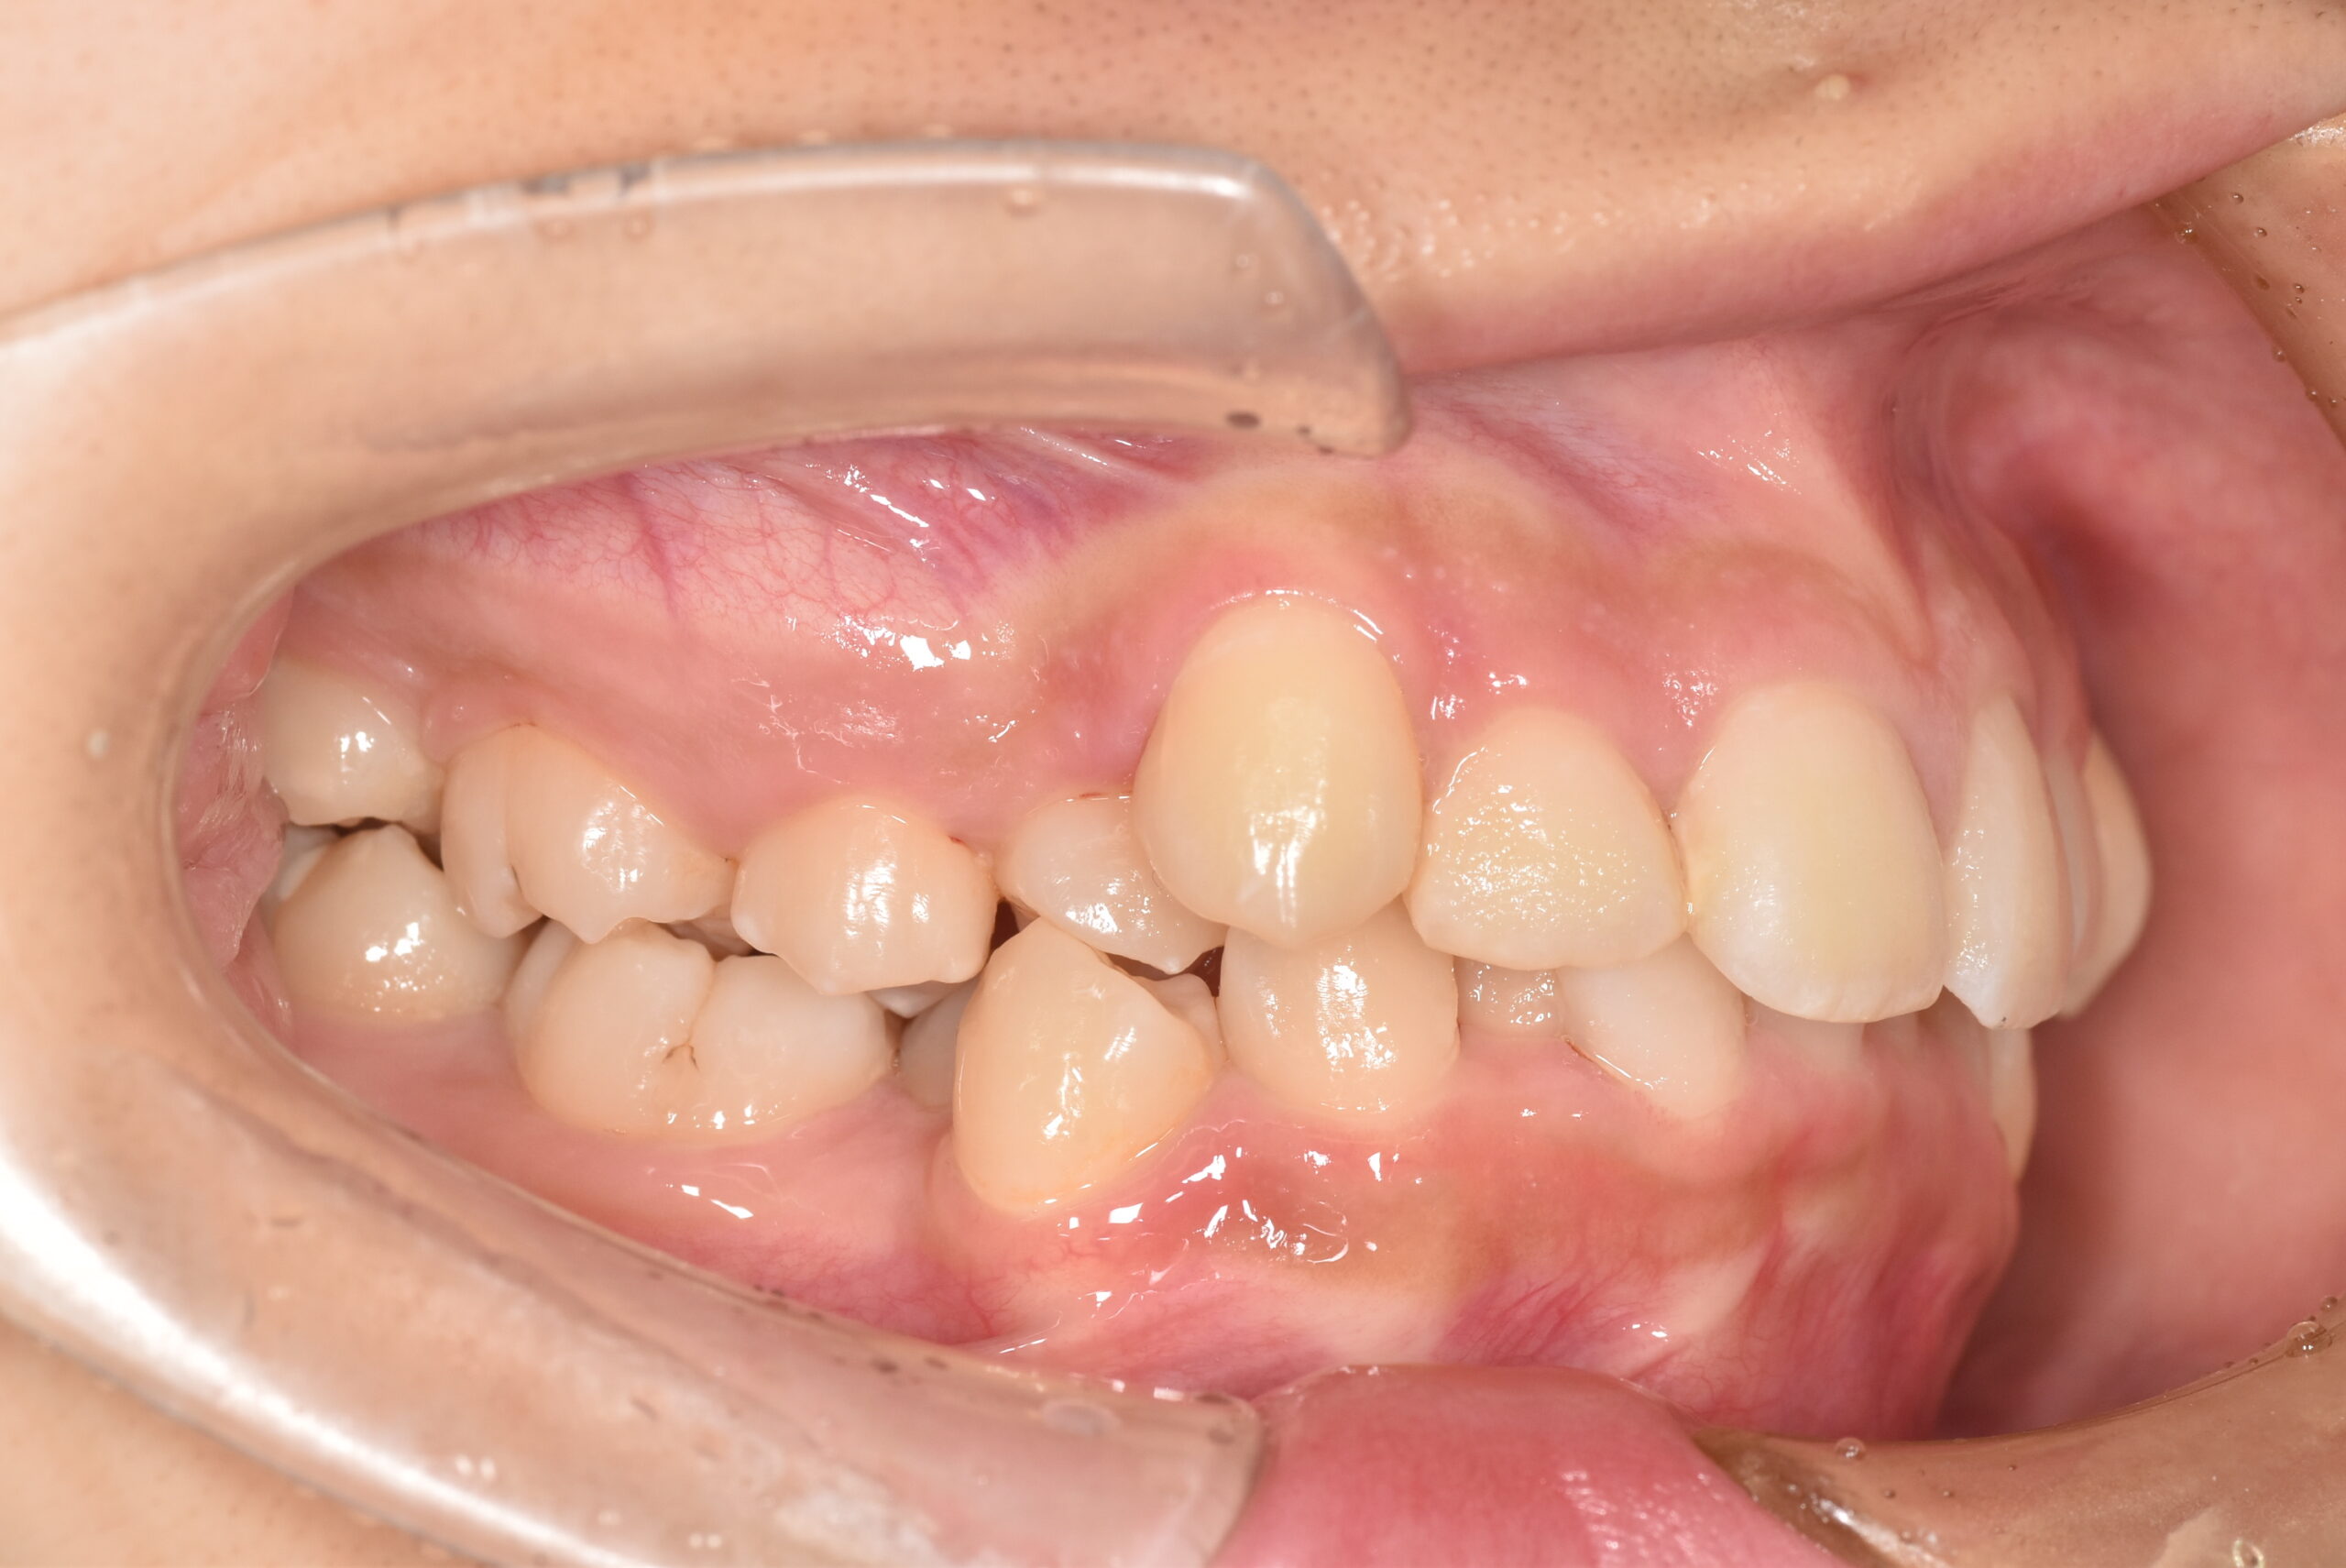

BEFORE

| 年齢 | 19歳 |

|---|---|

| 主訴 | ガタガタが気になる |

| 症状 | 過蓋咬合を伴う叢生症例 |

| 治療内容 | 過蓋咬合を伴う叢生症例と診断し上下顎両側第一小臼歯の抜歯を行い、マルチブラケット装置を用いて治療を行いました。上顎は裏側の矯正装置、下顎は表側の矯正装置で治療を行いました。ハーフリンガル矯正治療。 |

| 抜歯部位 | 上下顎両側第一小臼歯 |

| 治療期間 | 3年 |

| 費用(税込) | 1,045,000(税込)別途処置料 |

| 治療のリスク | 虫歯、歯周病の悪化、歯肉退縮、歯根吸収、顎関節症の悪化、後戻り |